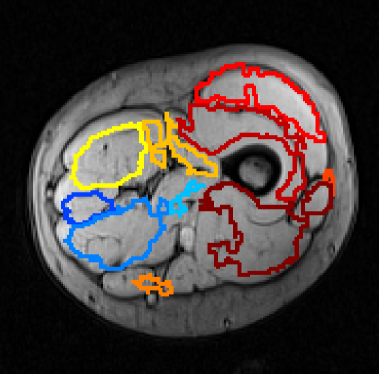

Refer to caption

Figure 4: Examples of AdaBoost muscle tissue segmentation results.

Mean and standard deviation of the mentioned performance measures were taken over a 10-fold cross-validation, and are presented in Fig. 3. Segmentation of the whole muscle region (Fig. 4) yielded mean Recall, Precision and Dice overlap coefficients of 0.81500.81500.8150, 0.74540.74540.7454 and 0.76230.76230.7623, respectively.

Average performance measures scored above 0.70.70.7, despite the variability on the results (Fig. 3). From the total 50 AdaBoost results obtained in cross-validation, the majority presented a correct identification of the muscle region, with proper tissue separation. Results with high recall rates tend to also increase the number of false positives (lower precision), as the example shown in Fig. 4(a). Using more features could improve the discriminative properties of the proposed classification scheme.

On the other hand, in some cases, the texture recognition failed to provide accurate results, as shown in Fig. 4(b), leading to low recall values. This figure shows the worst obtained result (corresponding to volume 10 in Fig. 3). An objective quality study may help to bring insight into a possible impact of texture quality on the recall rate of the proposed segmentation model.

There is a codependency between AdaBoost accuracy and the atlas transformation and placement. Using the proposed atlas approach to label the AdaBoost binary leads to reasonable results in segmented images with a low false positive rate. However, if false positives have an influence on the position of the most distal point relative to the bone centroid, as shown in the example in Fig. 4(a), the proposed method tends to produce an unreliable muscle labeling. In these cases, the atlas transformation is biased and leads to labels offset, even though the AdaBoost segmentation recall rate is high (Figs. 5(a) and (b)).